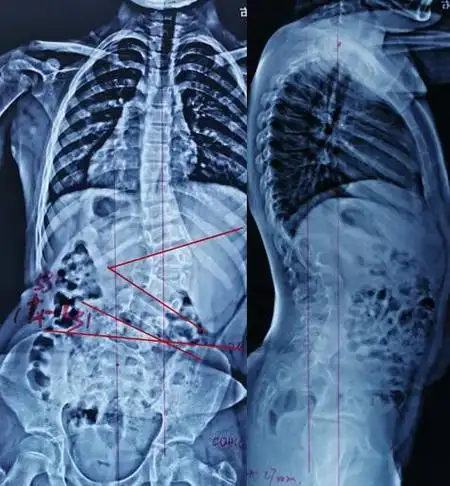

手术治疗先天性脊柱侧凸畸形脊髓纵裂病例分享